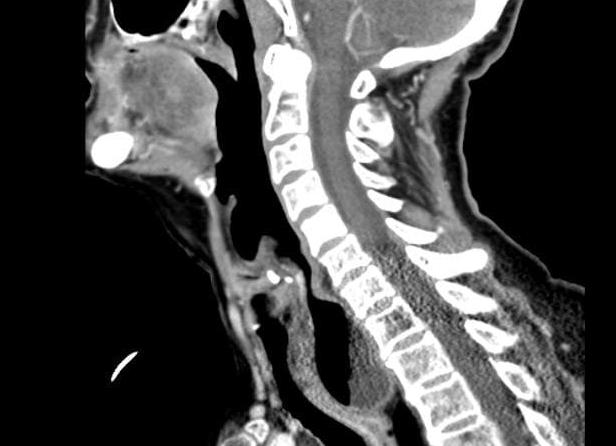

Компьютерная томография шейного отдела позвоночника предполагает использование специальной аппаратуры. Она показывает картину происходящего и дает возможность обнаружить патологические изменения даже на ранних стадиях. Изображения представляют собой срезы слой за слоем тела в заданной области. Чем плотнее ткань, тем светлее она будет на снимке. Кость имеет бесцветный оттенок, так как практически полностью впитывает ионизирующие лучи аппарата.

Полученные снимки отражают 1-3 мм ткани, если выбрать в настройках большую толщину, то информативность обследования существенно снижается. Современное оборудование, используемое в КТ-кабинетах, позволяет специалисту увидеть трехмерное изображение позвонков. Это предоставляет специалисту возможность рассмотреть проблемную область под разными углами, провернуть, приблизить ее или увеличить. Чем больше имеется информации об исследуемом органе, тем точнее будет постановка диагноза. Особенно это важно при травмировании шеи.

С помощью данной методики идет обследование позвоночника в области шеи. На основе полученных данных создаются трехмерная и двухмерная модели шейных позвонков, что облегчает исследование этого отдела. КТ является высокоточным рентгеновским обследованием, которое широко применяется в изучении костных повреждений и патологий мягких тканей.

Особенность такого подхода заключена в снятии многочисленных снимков при помощи томографа, который как бы «крутится» вокруг выбранной зоны обследования. Вслед за этим идет обработка на компьютере, благодаря чему снимки обретают свою четкость. Изображения позволяют вглядеться в мельчайшие подробности, размер самой мелкой детали может доходить до 0,5 мм. К тому же все снимки хранятся в «цифре». Их можно просмотреть в любой момент, развернуть под нужным углом и в требуемой плоскости.

Анализ дает возможность создать послойные снимки областей тела. Светлые и темные области изображений возникают вследствие разной способности задерживать лучи рентгена. К примеру, костная ткань будет светлой, поскольку у нее высокая способность к поглощению лучей.

Толщина срезов может варьироваться и составлять 1-3 мм. При большой толщине обследование не занимает много времени, но при этом снижается общая информативность. Сейчас аппараты дают возможность получать трехмерную модель нужного участка тела.